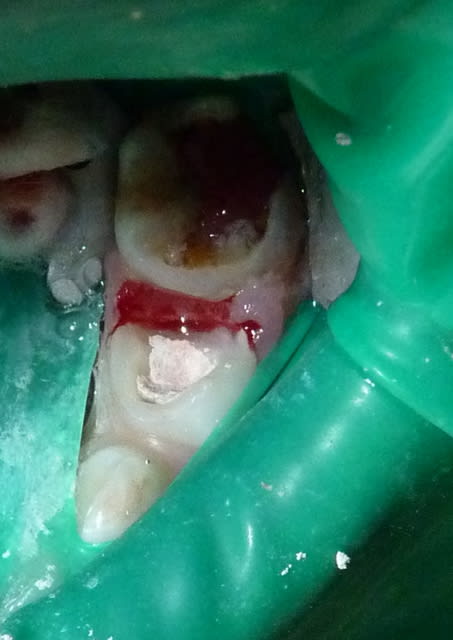

Dans le cas ci-dessous, la 1ère photo est prise après début d’éviction carieuse : sur la 4, on voit déjà la pulpe par transparence. Les tubuli dentinaires d'une dent temporaire sont beaucoup plus larges et nombreux que sur une dent permanente. Ainsi, une carie dentinaire infecte très rapidement la pulpe camérale. Faire une restauration sans pulpotomie dans ce cas aurait probablement abouti à une nécrose à moyen terme.